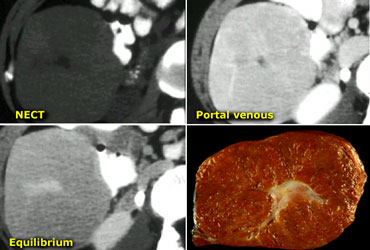

Giant hemangiomas with scar-tissue. Notice that the enhancement matches the bloodpool in all phases. Central scar is hypodens on NECT and stays hypodens. Giant hemangiomas with scar-tissue. Notice that the enhancement matches the bloodpool in all phases. Central scar is hypodens on NECT and stays hypodens.

Large hemangiomas can have an atypical appearance.

Complete fill in is sometimes prevented by central fibrous scarring.

These lesions need to be differentiated from other lesions with a scar like FLC, FNH and Cholangiocarcinoma.

Again looking at the bloodpool will help you.

On the left two large hemangiomas.

Notice that the enhancing parts of the lesion follow the bloodpool in every phase, but centrally there is scar tissue that does not enhance.